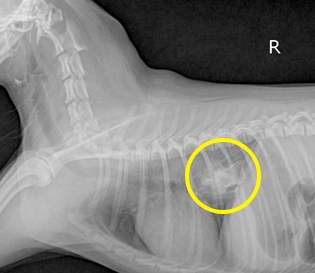

식도 내 이물